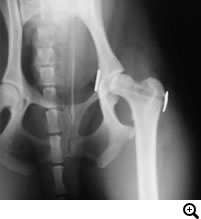

股関節形成不全症

股関節形成不全症とは

成長過程で股関節(寛骨と大腿骨)の発育異常が生じ、股関節に緩みが引き起こされる疾患です。緩みのある不安定な股関節を動かすことで、関節の軟骨部分が損傷を受け関節炎がはじまります。関節炎による痛みから跛行を呈します。

触診、レントゲン検査

• THR(Total Hip Replacement)/ 股関節全置換術

Micro THR(Micro Total Hip Replacement)/ 小型犬・猫用股関節全置換術

• DPO(Double Pelvic Osteotomy)/ 二点骨盤骨切り術

TPO(Triple Pelvic Osteotomy)/ 三点骨盤骨切り術

• FHO(Femoral Head Osteotomy)/ 骨頭切除術

• JPS(Juvenile Pubic Symphysiodesis)/ 若齢期恥骨結合固定術